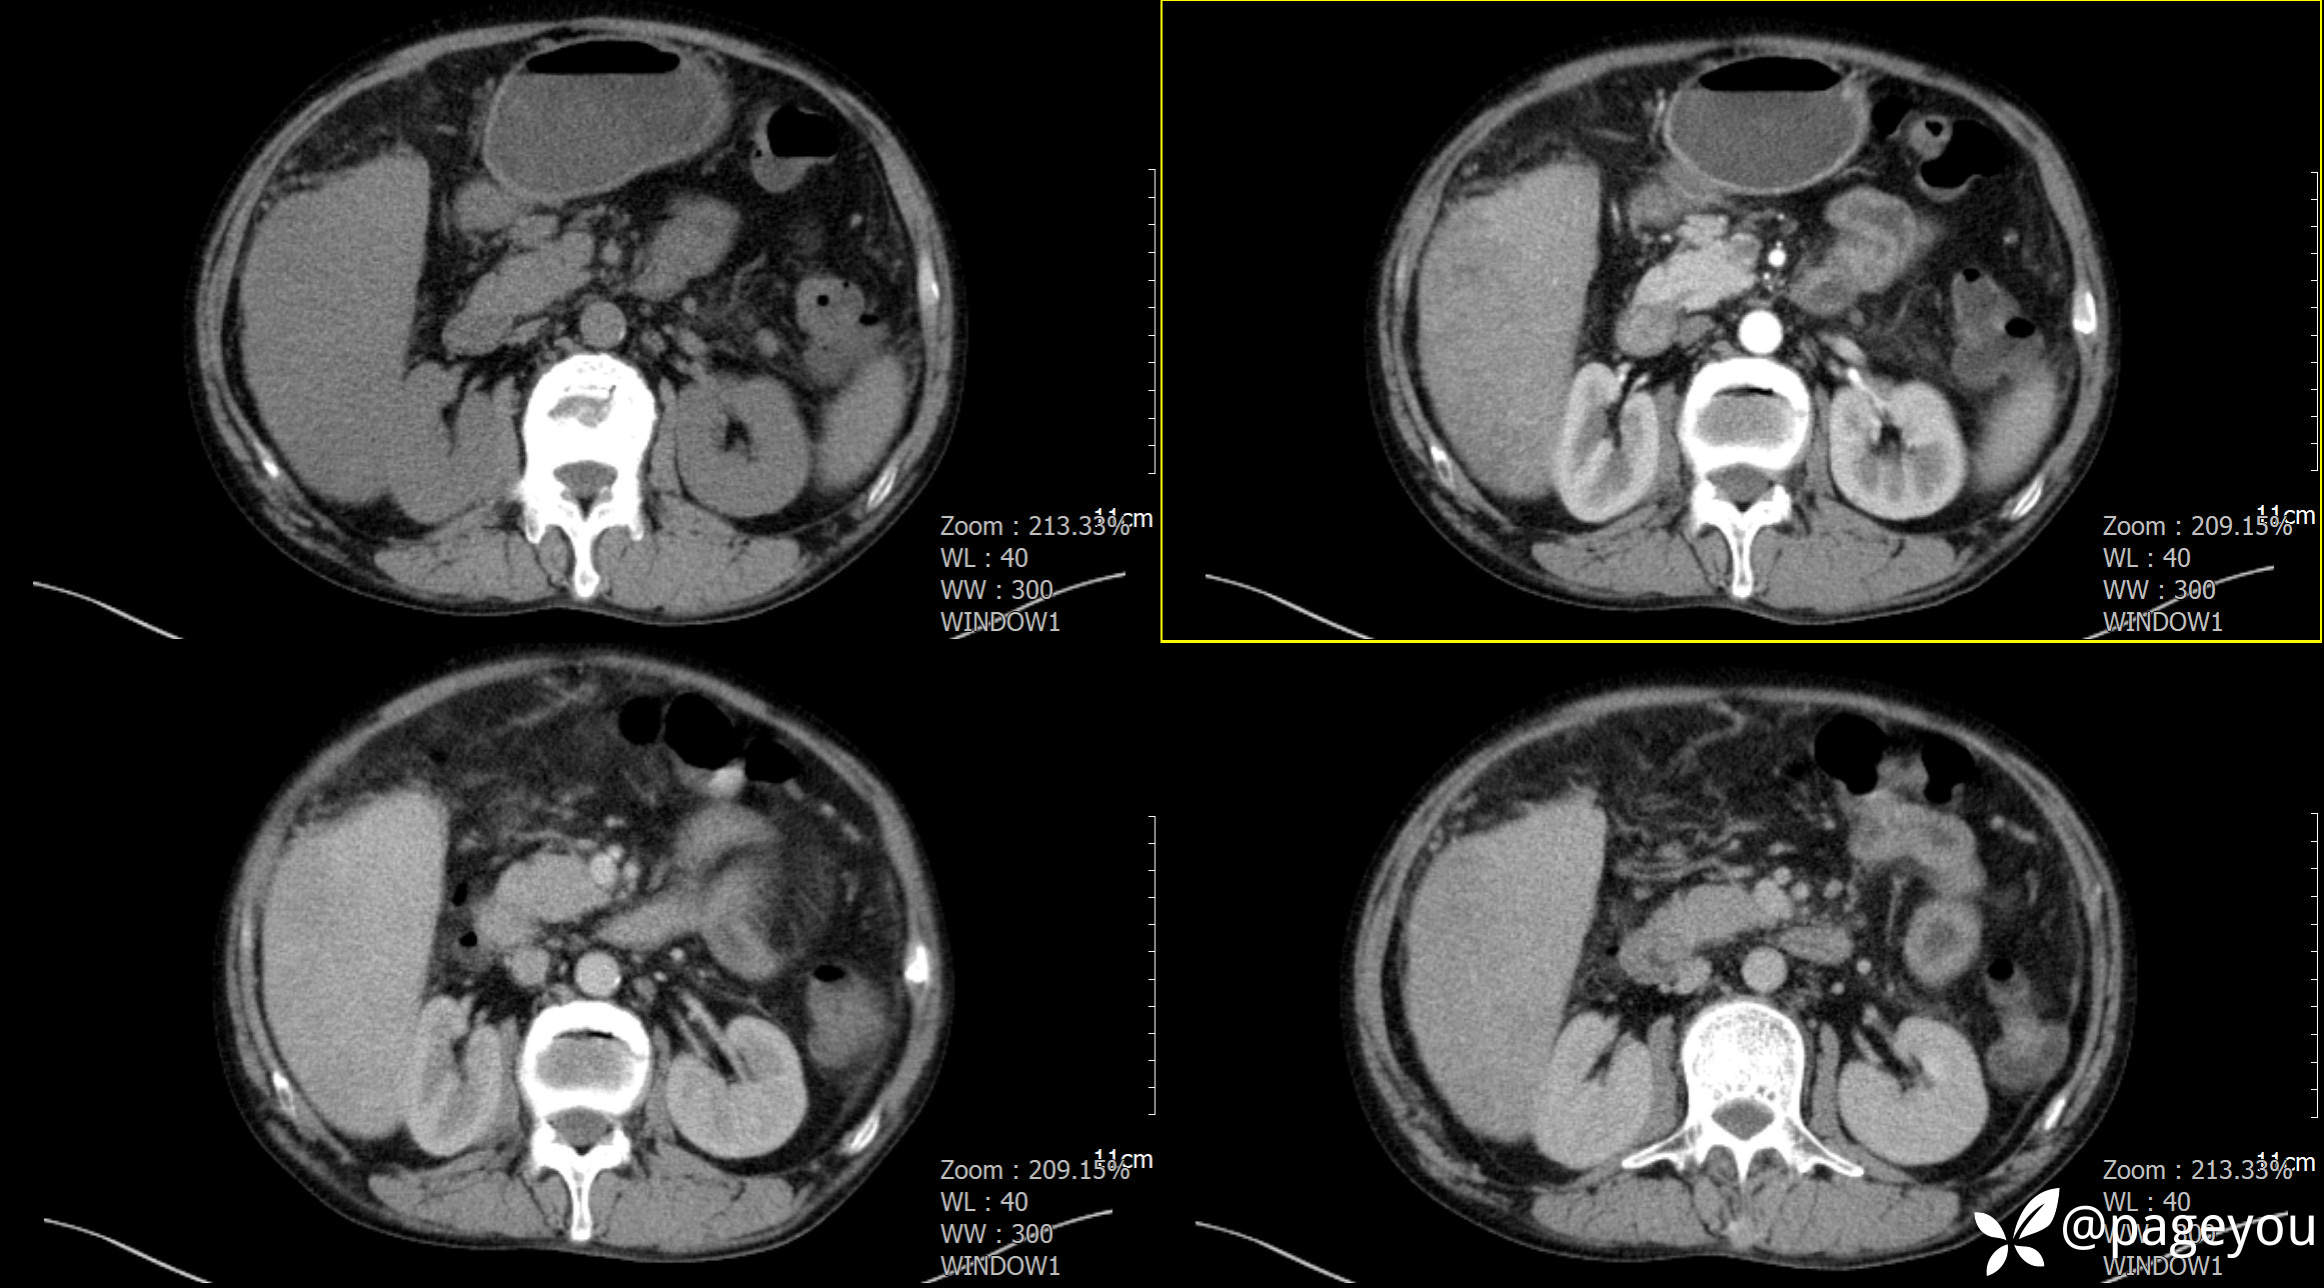

CT检查: